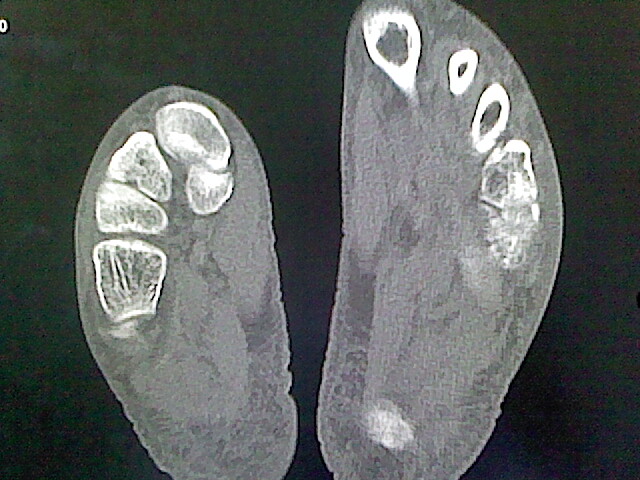

标题: CT16814:男,76岁,左小腿疼痛,不能站立 大家给看看 [打印本页]

男,76岁,左小腿疼痛,不能站立

本例骨质改变主要表现为滑膜或韧带区的骨侵蚀融解(胫腓联合区骨质破坏无硬化边),距骨后部骨质破坏区有硬化边及死骨样改变.所以,本例考虑关节结核可能性大,绒毛膜结节性滑膜炎多发于中年,且极少见于膝髋以外的关节,骨质硬坏也以压陷吸收为主,有明显的硬化边,骨膜增生呈结节状(可以mr鉴别),所以本例暂除外.

另不除外可引起相似表现的其他炎症如布氏杆菌性关节炎等